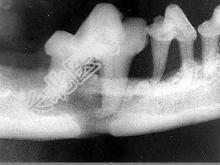

- 单项选择题颌面外伤患者,咬合错乱, 下唇麻木张口受限,经X 线检查如图。应该为 ( )

A、上颌骨骨折

B、颧骨骨折

C、颧弓骨折

D、下颌骨骨折

E、牙槽突骨折